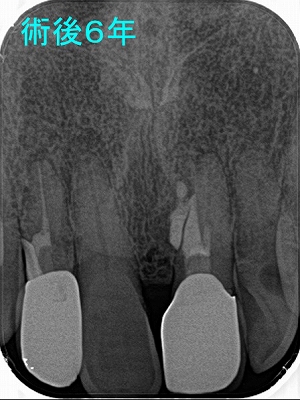

先日、治療した歯の調子がわるいという患者さん

ん~、水酸化カルシュウムが歯の外に押し出しているように見えます。

歯の外に押し出しても吸収して骨に変わることはありません。

そもそも論なんですが、根尖病変の原因は細菌感染でその結果として骨の吸収が起こります。

つまり溶けた骨にアプローチしても殆ど意味ありません。。。